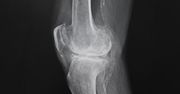

Choroba Scheuermanna - przyczyny, objawy, leczenie

Choroba Scheuermanna, czyli jałowa martwica kręgosłupa, jest wciąż zagadką dla lekarzy i naukowców. Wprawdzie nietrudno ją rozpoznać i znane są metody jej leczenia, ale przyczyny choroby są nieznane. Nie bez przyczyny nazywana jest także młodzieńczą kifozą – występuje najczęściej u młodych, nastoletnich osób, jeszcze przed okresem pokwitania.